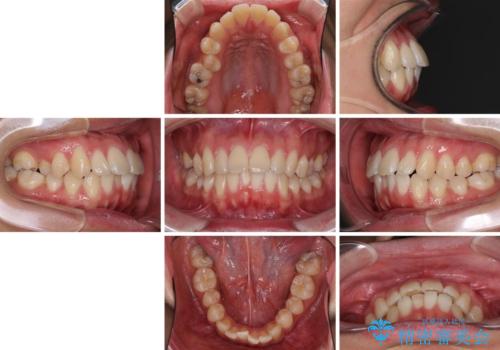

- 全体的なデコボコと、前歯の前に出ている感じを気にして来院された患者様です。

患者様と相談の上、非抜歯にてインビザラインを用いて矯正治療を行うこととし、IPR(歯と歯の間)並びに歯列全体の後方移動により口元の突出感の改善することとしました。

お仕事が忙しい方で、装着時間が不足したり、定期的な通院ができなかったりと、自己管理が重要なインビザラインによる矯正治療が長期化する要因が重なり、5年ほどの期間を要しました。